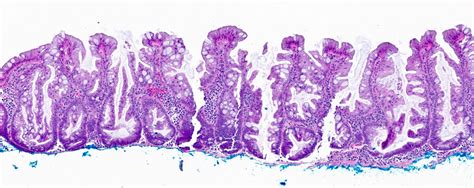

To understand a Sessile Serrated Adenoma, it helps to break down the medical terminology. "Sessile" indicates that the growth is flat or broad-based, rather than having a stalk like a mushroom. "Serrated" refers to the saw-toothed appearance of the cells when viewed under a microscope. Finally, an "adenoma" is a type of tumor, though in the context of colon polyps, it refers to a non-cancerous growth that, if left alone, may undergo genetic changes leading to malignancy.

The diagnosis is made definitively during a colonoscopy. If your doctor spots a lesion, they will perform a polypectomy (the removal of the polyp) using specialized instruments passed through the colonoscope. The removed tissue is then sent to a pathology lab where a pathologist examines the cells under a microscope to confirm the diagnosis and ensure the margins are clear.

• sessile serrated adenoma histology